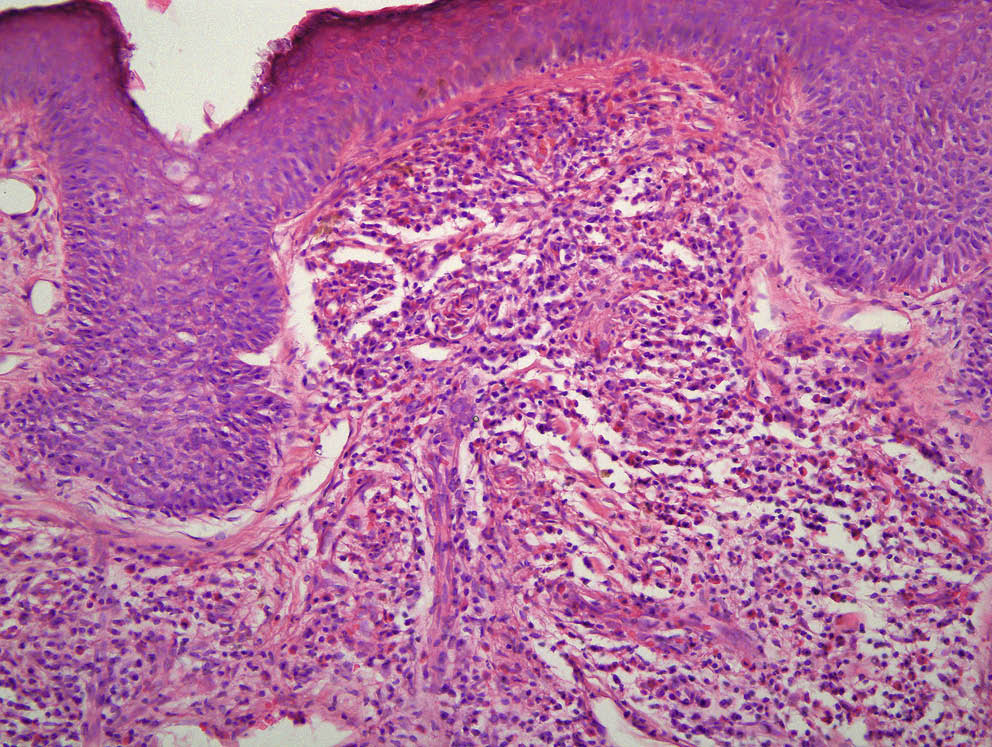

Пациенту была выполнена диагностическая биопсия кожи. При гистологическом исследовании в дерме и верхних отделах подкожной жировой клетчатки были обнаружены перифолликулярные и периваскулярные очаговые инфильтраты, состоящие из лимфоцитов, гистиоцитов и значительного количества нейтрофильных и эозинофильных лейкоцитов. Эндотелий сосудов был отечен, имелись сосуды с фибриноидным набуханием стенок (рис. 4).

Рис. 4. В эпидермисе умеренный акантоз, вакуольная дистрофия клеток мальпигиевого слоя. Верхнюю половину дермы занимает полосовидный инфильтрат, мелкие очаговые инфильтраты также обнаруживаются в нижней части дермы и подкожной жировой клетчатки вокруг волосяных фолликулов и периваскулярно. Инфильтрат состоит из значительного количества нейтрофильных и эозинофильных лейкоцитов. Нейтрофильные лейкоциты локализуются вокруг сосудов с очаговой умеренной лейкоцитоклазией. Эндотелий сосудов отечен, имеются сосуды с фибриноидным набуханием стенок

Fig. 4. In in the epidermis there is acanthosis and vacuolar dystrophy of the malpighiaceae layer. The top half of the dermis is filled with a line-like infiltrate, small focal infiltrate can also be seen in the lower part of the dermis and in the subcutaneous fat around hair follicles and blood vessels. Infiltrate consists of a significant number of neutrophilic and eosinophilic leukocytes. Neutrophilic leukocytes appear around blood vessels with focal mild leukocytoclasis. Vascular endothelial is swallen, there are vessels with fibrinoid swelling of the walls